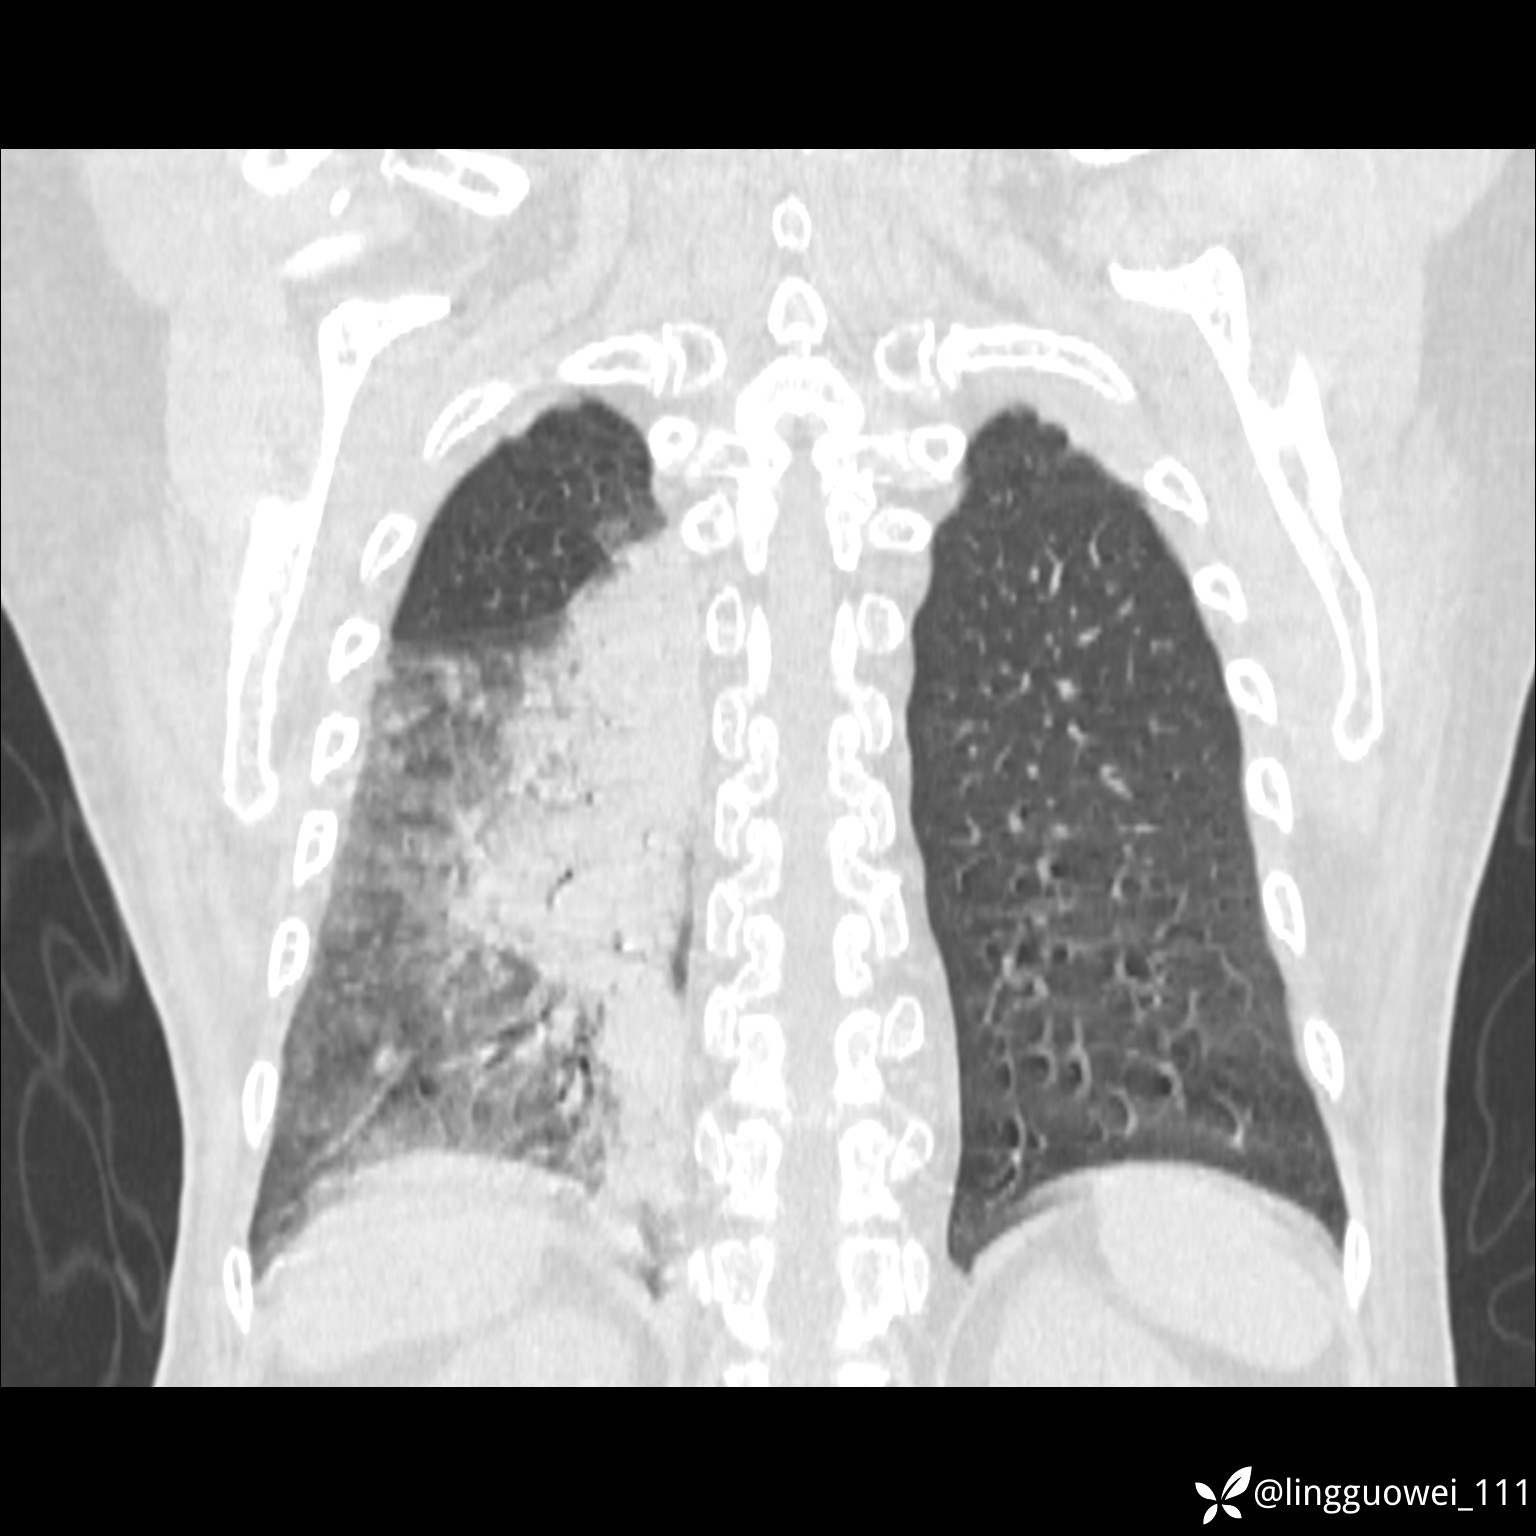

20小时后,行胸部增强检查,病灶范围较前增大